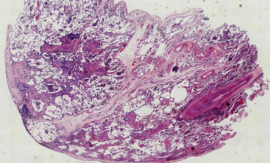

肺组织病理中,非纤维化型HP包括细胞性间质性肺炎(可见细支气管中心性分布,细胞性NSIP型,以淋巴细胞为著)、细胞性细支气管炎、未形成非坏死性肉芽肿(与结节病的肉芽肿呈显著差别)。纤维化型HP包括慢性纤维化性间质性肺炎(结构扭曲、成纤维细胞灶±胸膜下蜂窝肺纤维化性NSIP型)、气道中心性纤维化。

比如细胞性细支气管炎(下图左),可以看到很多淋巴细胞浸润;还有非坏死性肉芽肿炎(下图中),肉芽肿的边界并不清楚,有一些内上皮细胞和炎症浸润;细胞性慢性间质性肺炎——「NSIP样改变」(下图右)。